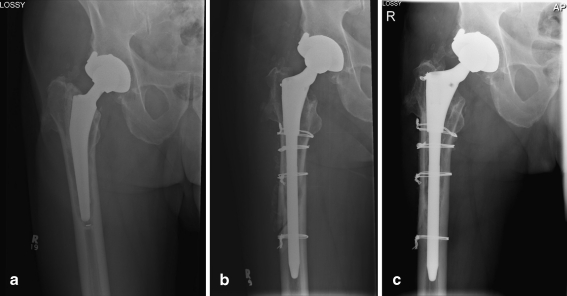

Fig. 1.

a An 83-year-old man with a loose cemented stem. b The stem was revised through an 18-cm extended trochanteric osteotomy. Five centimetres of scratch-fit were available for distal stem fixation. c Five years after revision, the stem is well fixed and the extended trochanteric osteotomy has healed